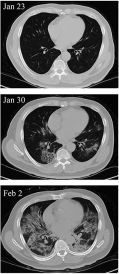

In this section we will focus on an example based on the COVID-19 pneumonia invading and fading away process in a patient’s lung reflected on CT scan images and try to show the possible COVID-19 pneumonia growth dynamics with time before and after the treatment. In order to fulfill the task, two parts of simulations are presented. In the first part, two CT scan images taken on a patient’s lungs in the beginning (January 23th) and severe state (February 2nd) of the disease [ZL20] are selected to be the initial and equilibrium state, respectively; see Fig. 3 (left). In the second part, two scan images at the severe state (February 2nd) and after a few-days’ treatment (February 9th) are selected to be the initial and equilibrium state, respectively; see Fig. 3 (right). Each CT scan image can be represented by a gray scale image matrix thus the same method in Example I can be applied. The CT scan images are all cropped to 461 pixels in width and 370 pixels in height, which means a total of 170570 pixel points in each image. The time step is and the total number of iterations is thus the final iteration time . The resolutions are .

After 6000 iterations, the relative root mean square errors from two parts of simulations both decrease with an exponential rate, as is shown in Fig. 4. Moreover, the image evolution after step 20, 50, 100, , , 1000, 5000, 10000 (see Fig. 5) clearly demonstrate the pneumonia invading process into the patient’s lungs caused by COVID-19 in a few days (upper group of figures in Fig. 5) and the pneumonia fading away from the lungs after a stem cell treatment is applied to the patient (lower group of figures in Fig. 5), indicating a potential success of this treatment [ZL20]. We can further compare the evolution process with the real CT scan images taken on January 30th (see Fig. 3) and find satisfactory agreements, which indicates promising applications in this field.